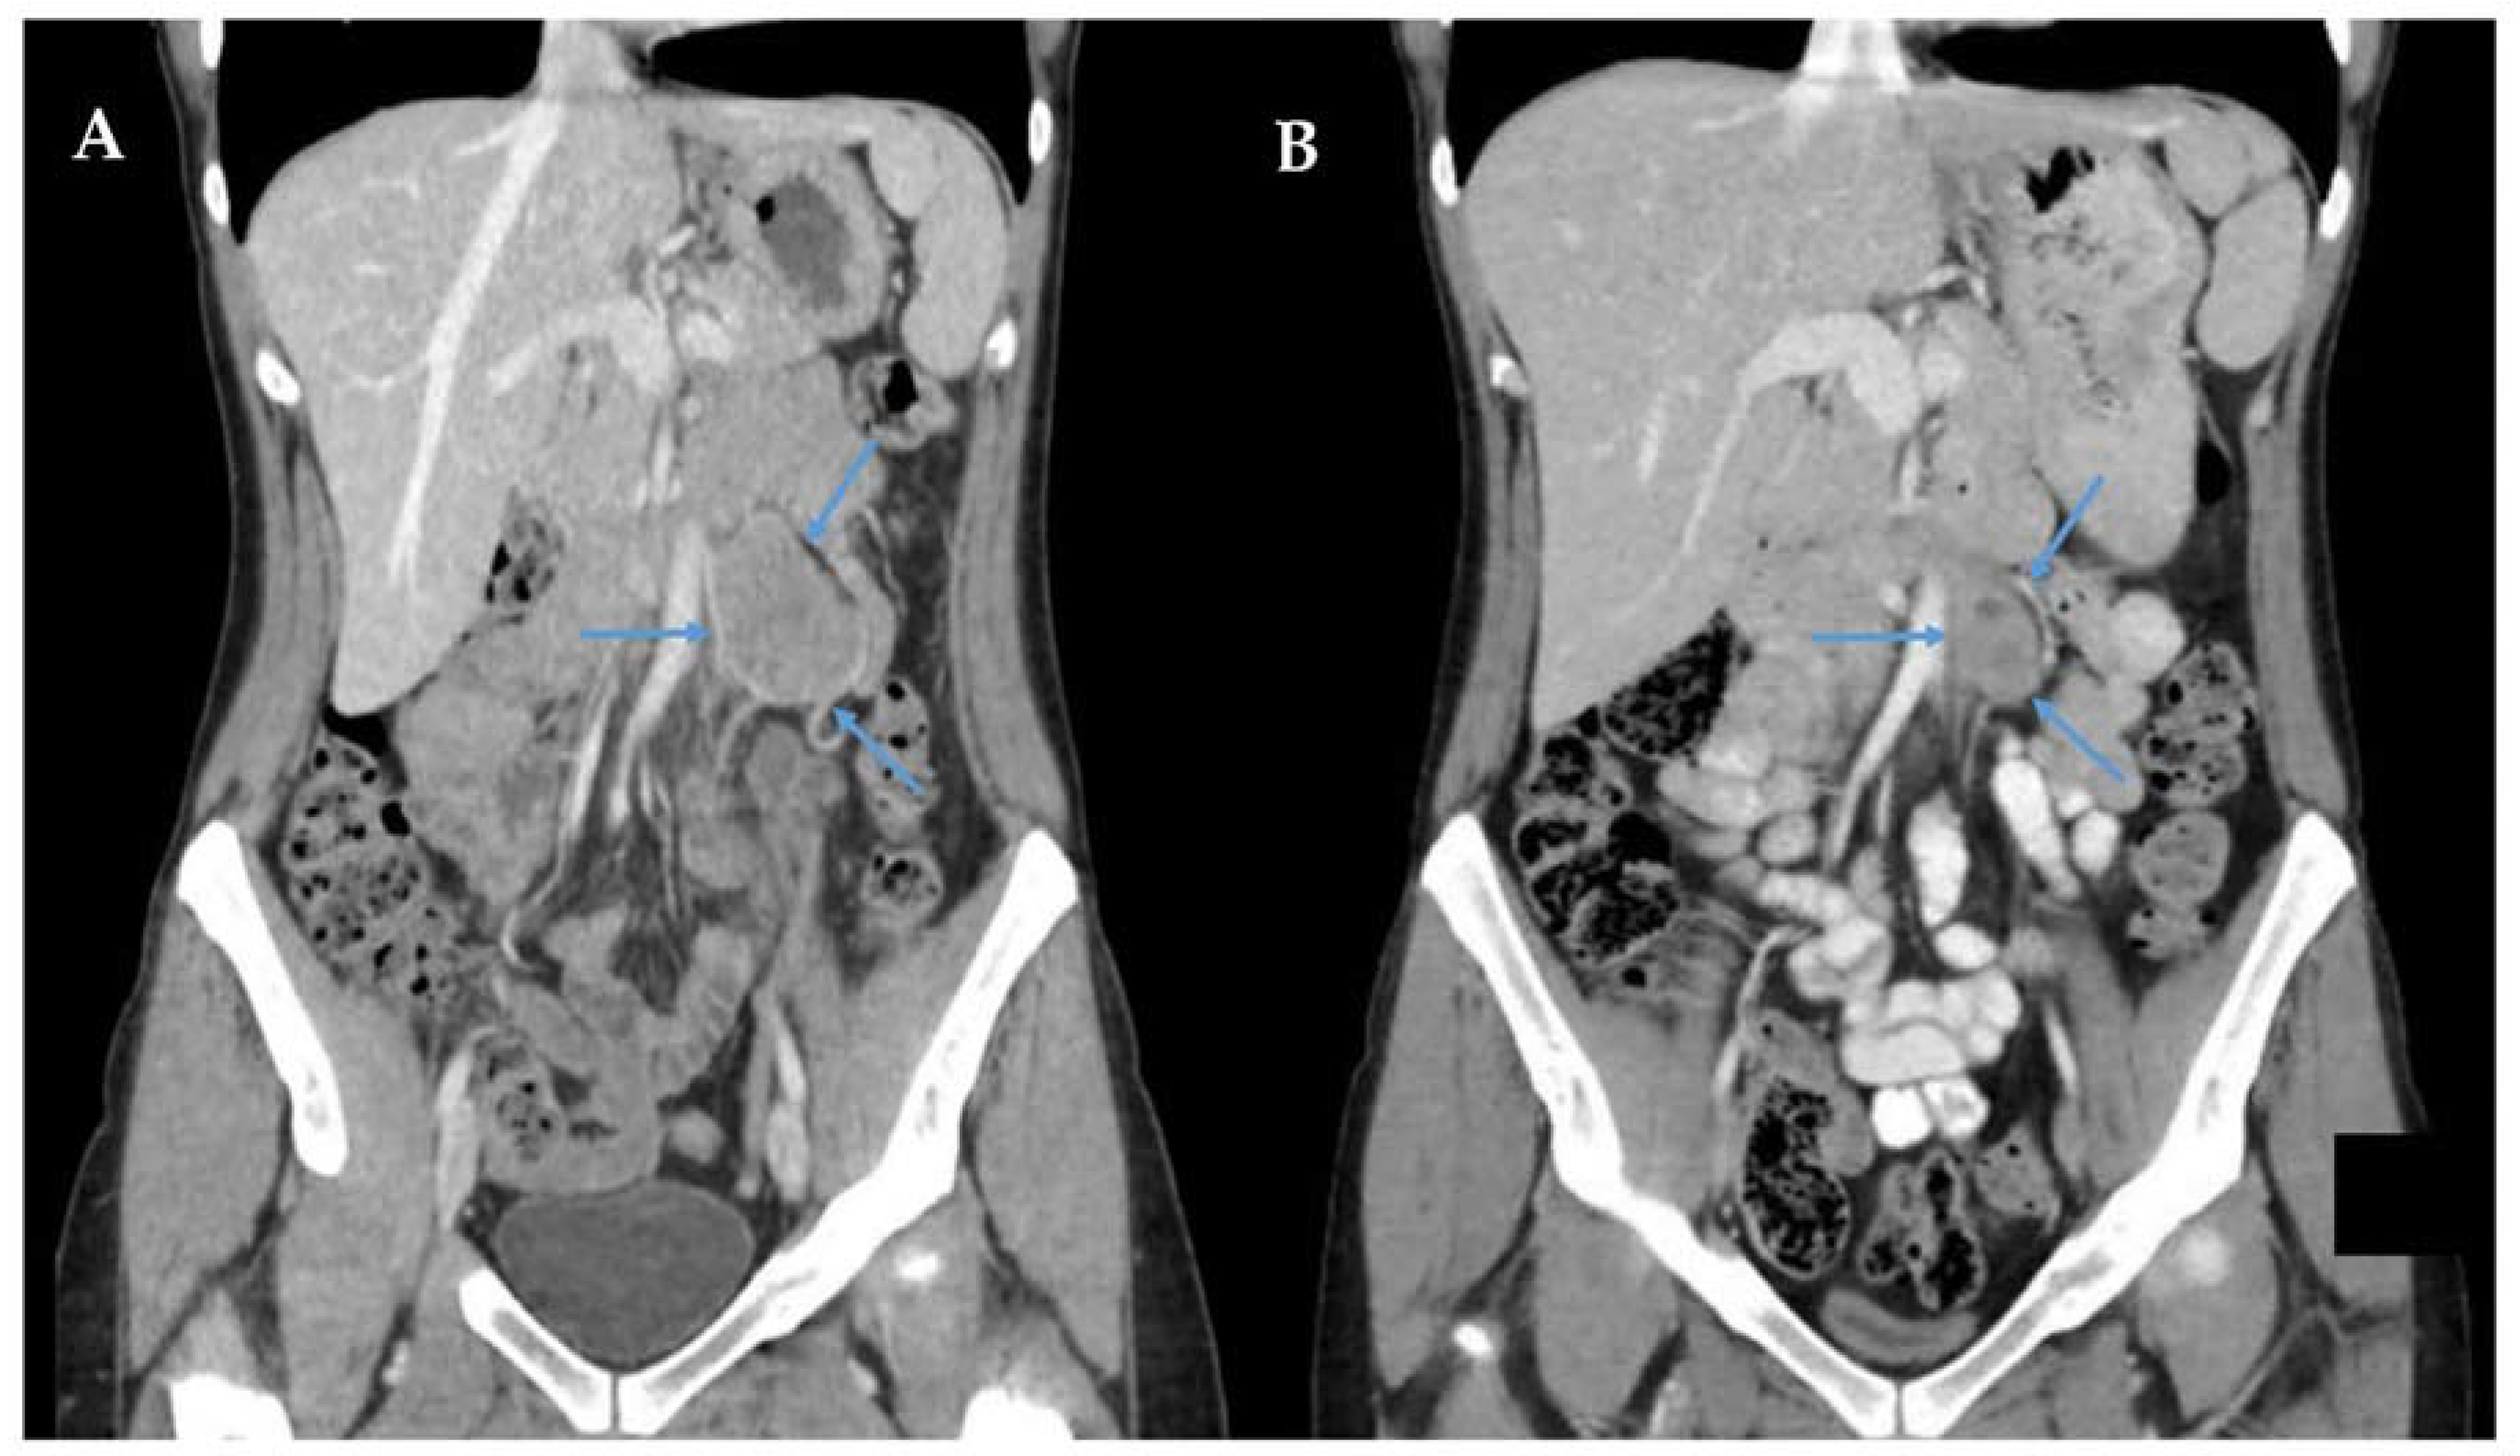

- Yim, H.; Tang, Y.L.; Tandon, A.A. Multifocal Retroperitoneal and Pelvic PEComas Mimicking Liposarcoma: A Case Report and Review of Literature. Radiol. Case Rep. 2021, 16, 2624–2629. [Google Scholar] [CrossRef]